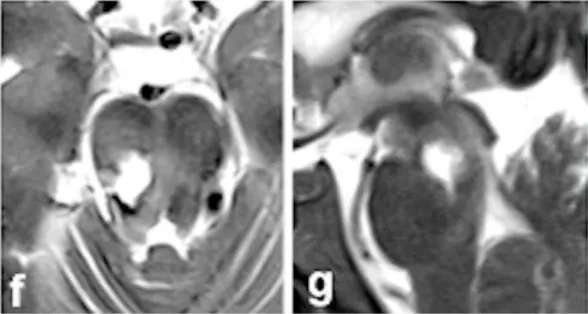

面对危急病情,巴教授果断制定手术方案,术中,巴教授凭借30余年的脑干手术经验,在显微镜下精细操作,选择经右侧颞下入路实施手术。最终将出血性病灶完整切除,术中全程未损伤关键神经和血管。

术后影像(图f-g)和术中记录共同证实,病灶已实现全切,出血得到彻底控制。

令人振奋的是,Jack在术后恢复迅速,神经功能障碍逐渐改善。经过规范康复和随访,术后6个月时,他已经重新回归正常生活和工作。